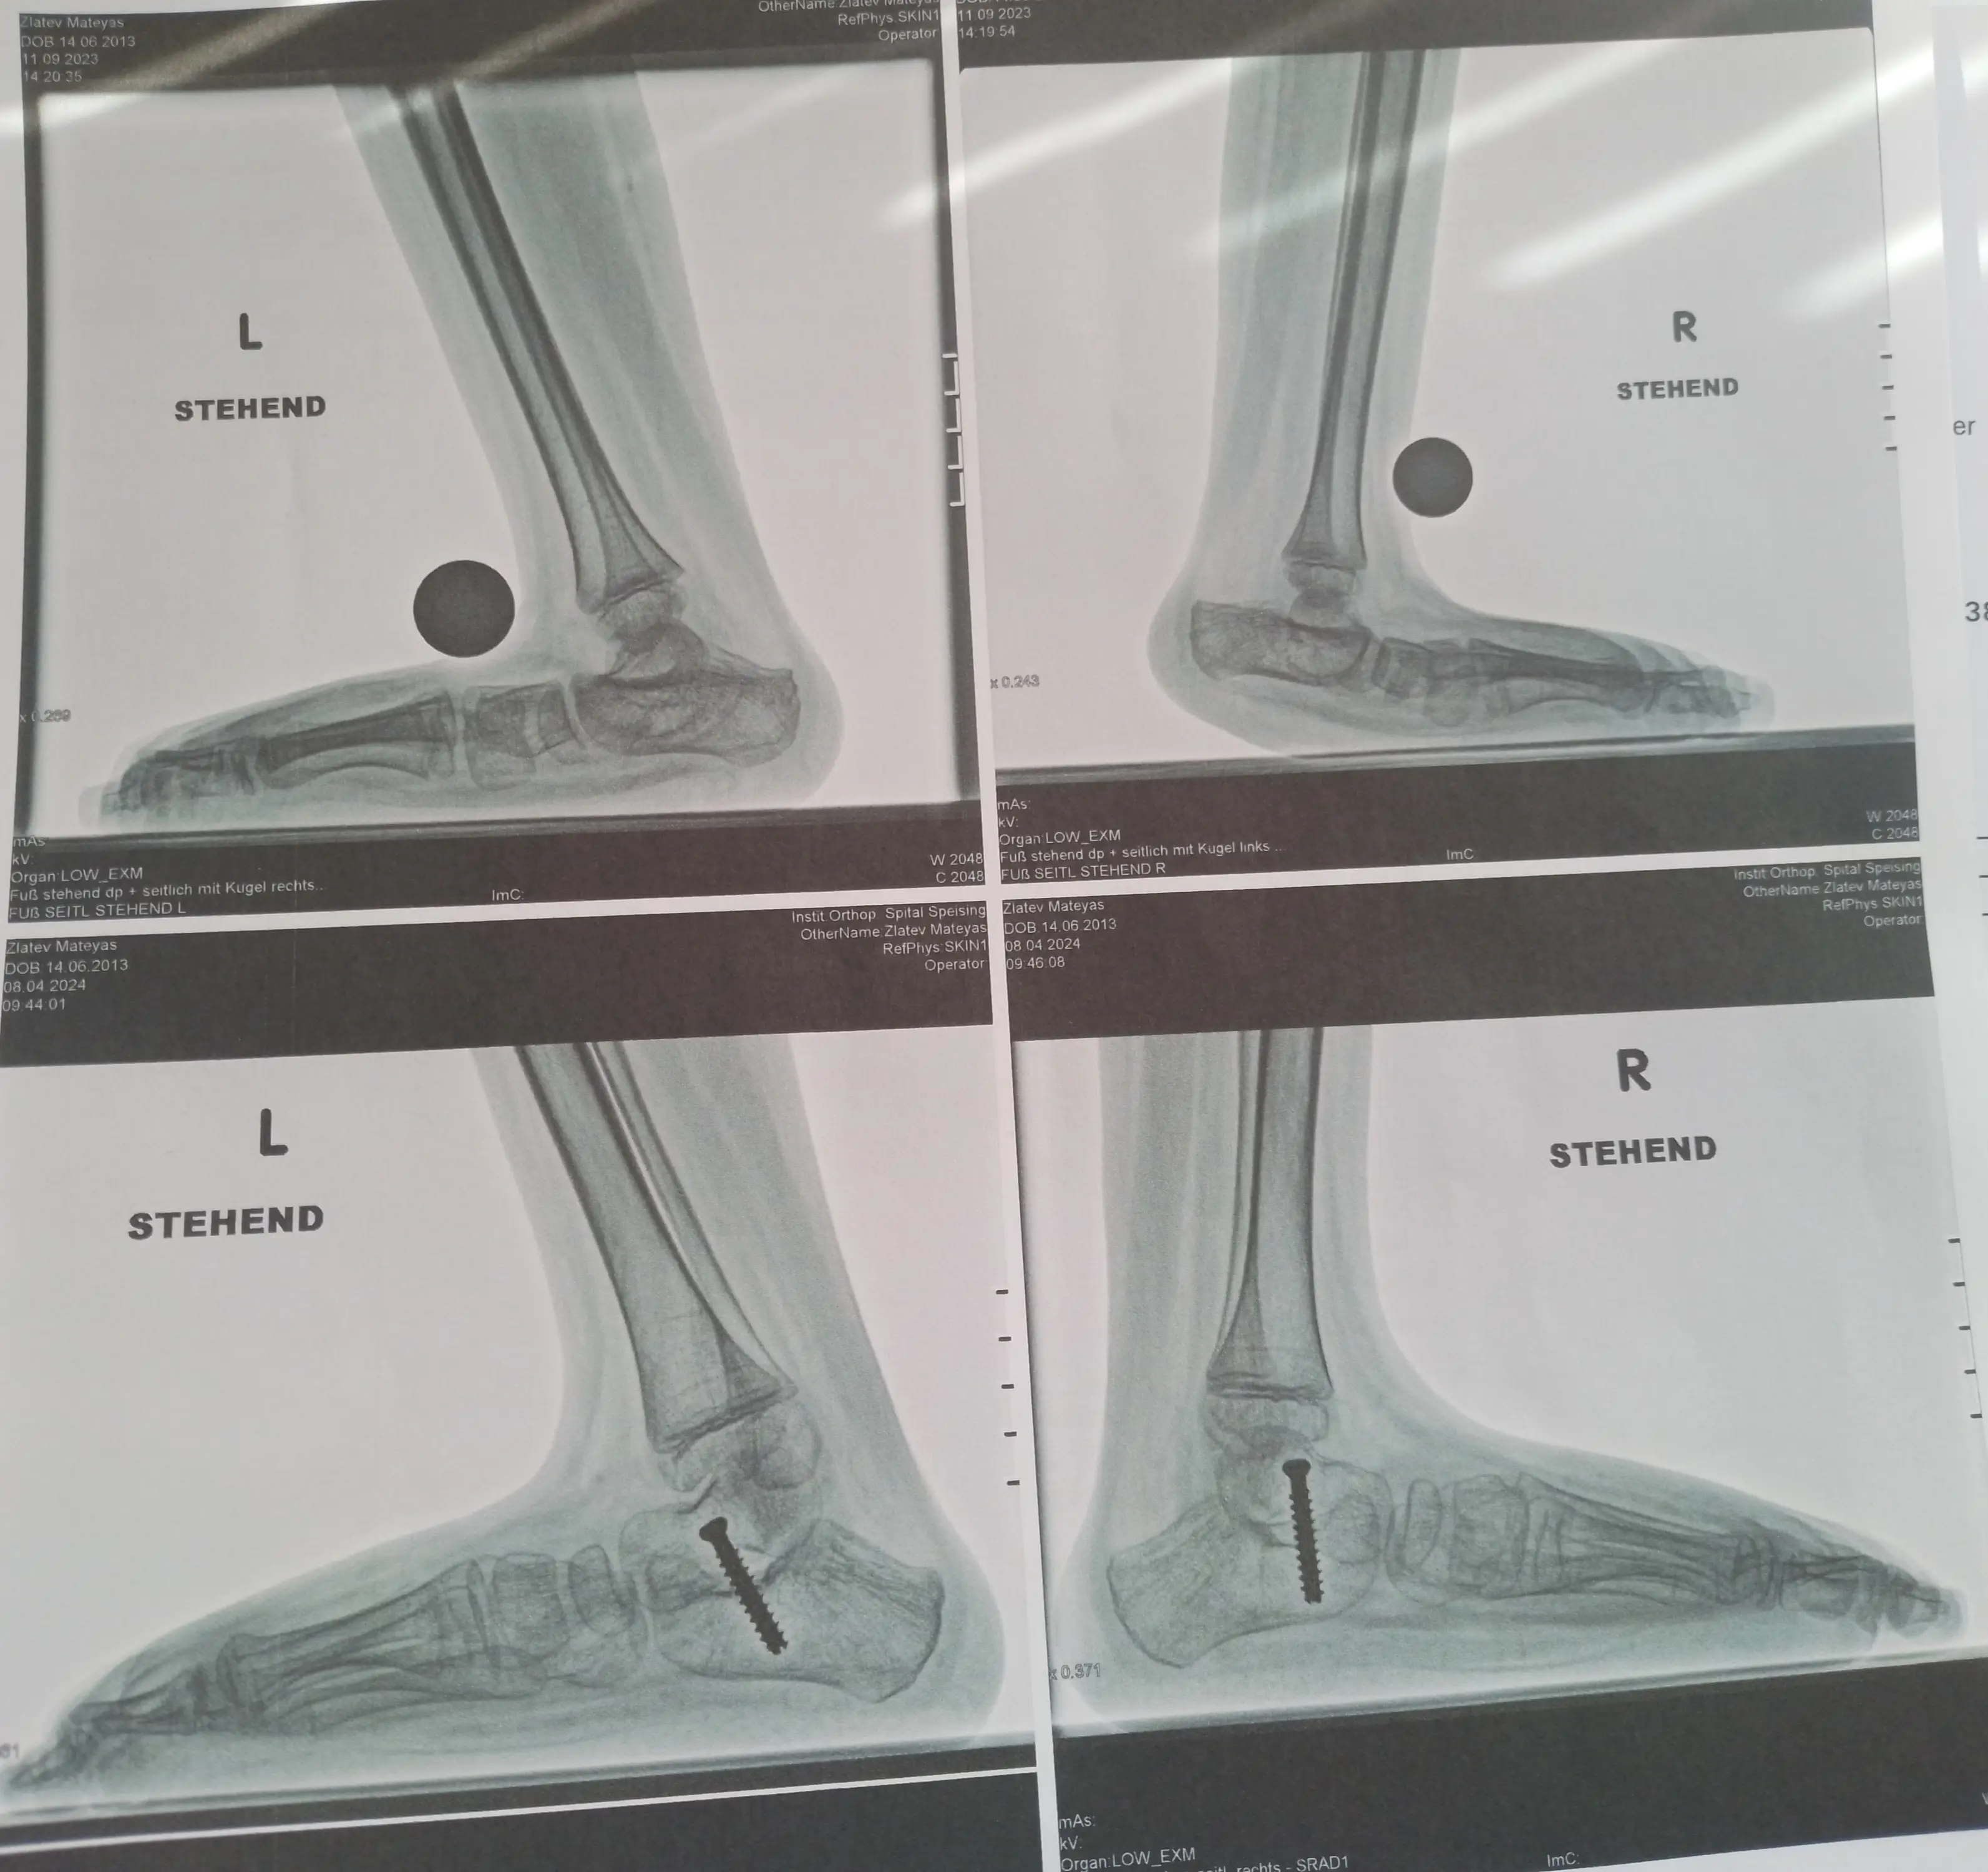

На 08.04.2024 бяхме на контролен преглед в Виена болница Шпайзинг при д-р Кребс. Минаха 6 месеца от операциите който Матеяс претърпя на свойте крачета веднъж 10 операции. Матеяс се възстановява по добре от очакваното. Лекаря му направи 4 бр рентгенови снимки и ни каза че към момента лечението върви по добре от очакваното и че не е очаквал такива добри и бързи резултати.

On 08.04.2024 we had a check-up in Vienna Hospital Speising with Dr. Krebs. It's been 6 months since Mateias had 10 operations on his legs. Mateias is recovering better than expected. The doctor took 4 x-rays and told us that the treatment is going better than expected and that he did not expect such good and fast results.